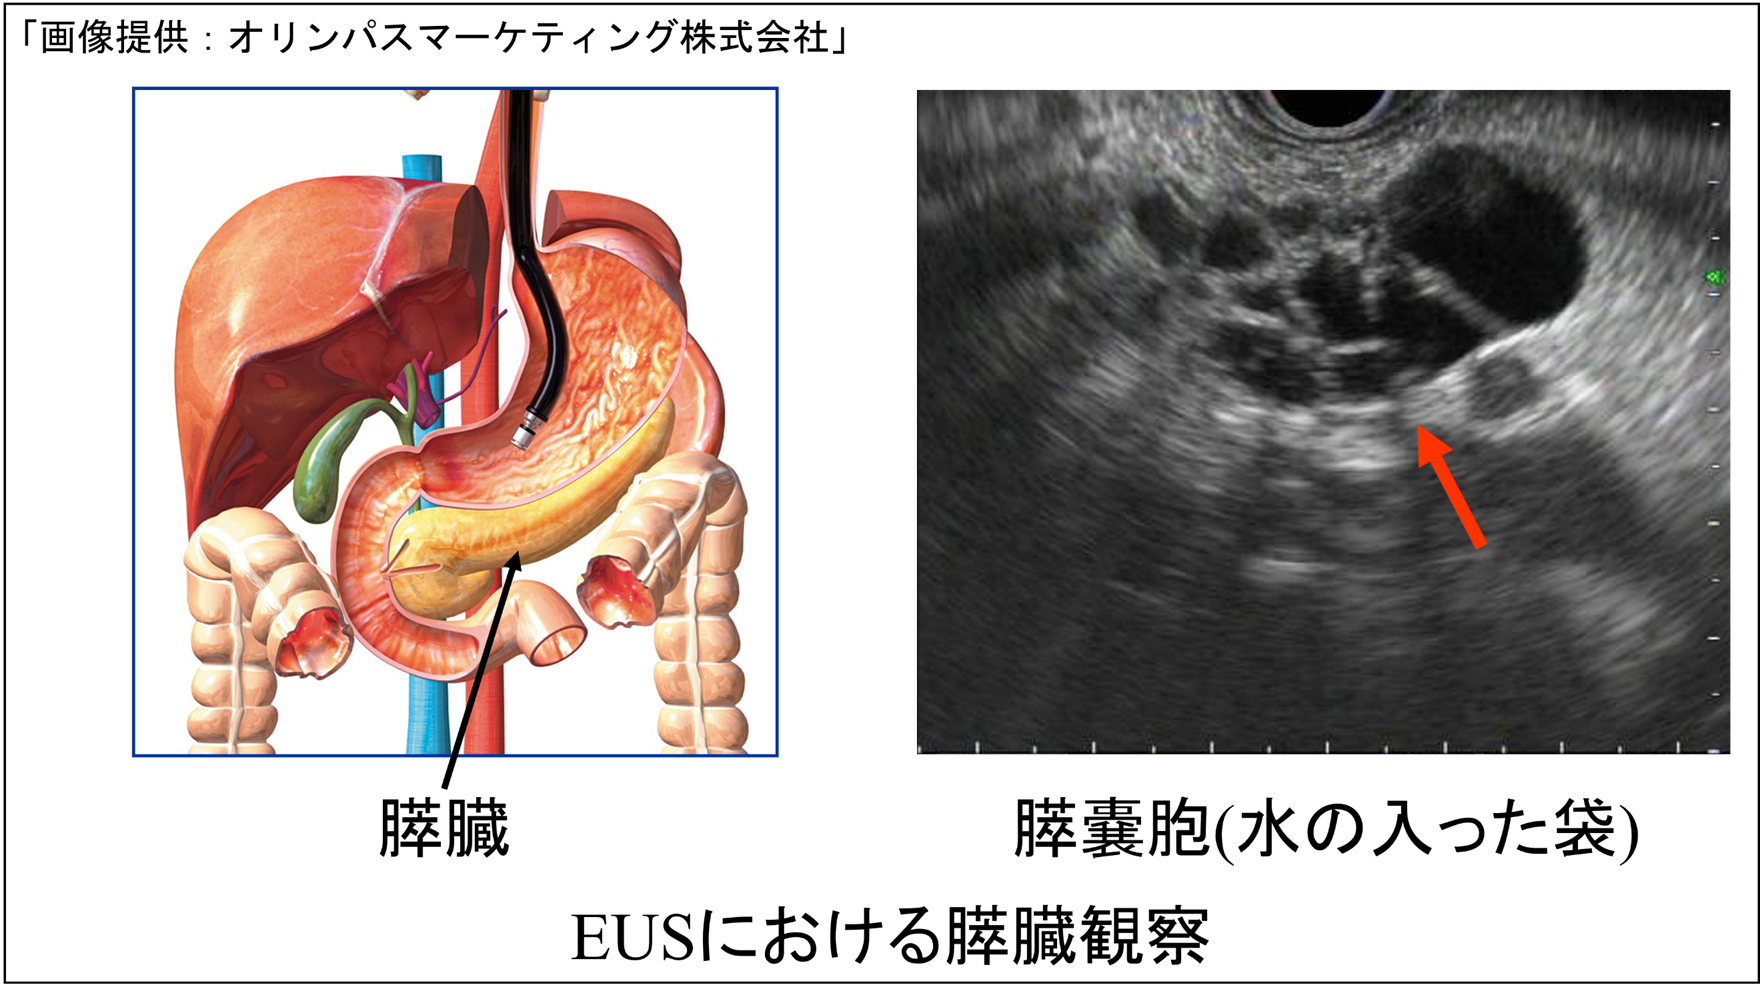

(2)超音波内視鏡(EUS)

EUSは、先端に超音波装置が付いた特殊な内視鏡を口から胃・十二指腸に入れ、胆嚢・胆管・膵臓を観察する検査です。お腹の上から行う超音波では、胃や腸のガスが邪魔になり、膵臓や胆管を細かく見るのが難しいことがあります。EUSは胃や十二指腸の中から近い距離で超音波を当てるため、ガスの影響を受けにくく、膵臓や胆管を詳しく観察できます。胆嚢ポリープ、総胆管結石、胆管腫瘍、膵嚢胞、膵腫瘍などの精密な評価が可能です。さらに、スコープの先から細い針を出し、消化管の外にある病変から組織を採る超音波内視鏡下穿刺吸引法(EUS-FNA)も行われます。EUSで膵腫瘍やリンパ節の腫れが見つかったときなどに行う検査です。